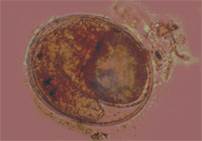

Nang ấu trùng trong cá